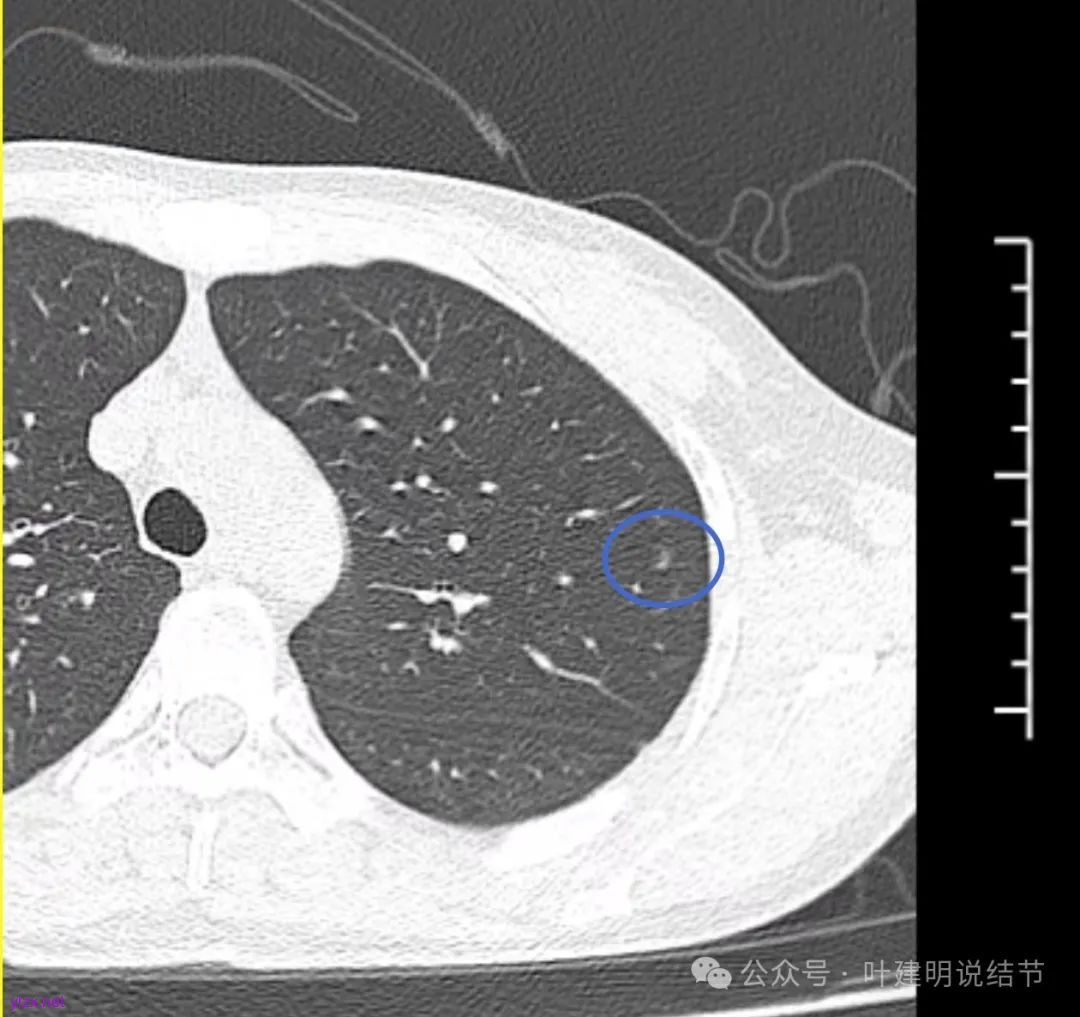

右下此灶2023年时此层面淡而边显糊。

上图层面已经像混合密度了,表面毛糙不光滑,灶内密度不均,也有小空泡征的样子。

感觉这处(在上截图结节的下面点,邻近层面)不像前面病灶的延伸,否则这密度的变化有点突兀呀。